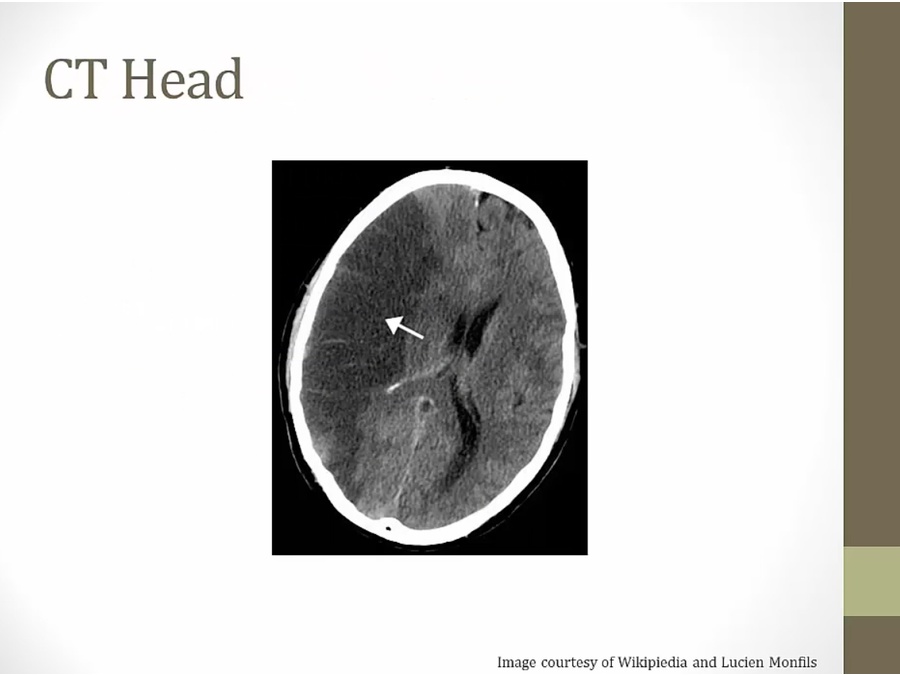

Lacunar Stroke

Locations